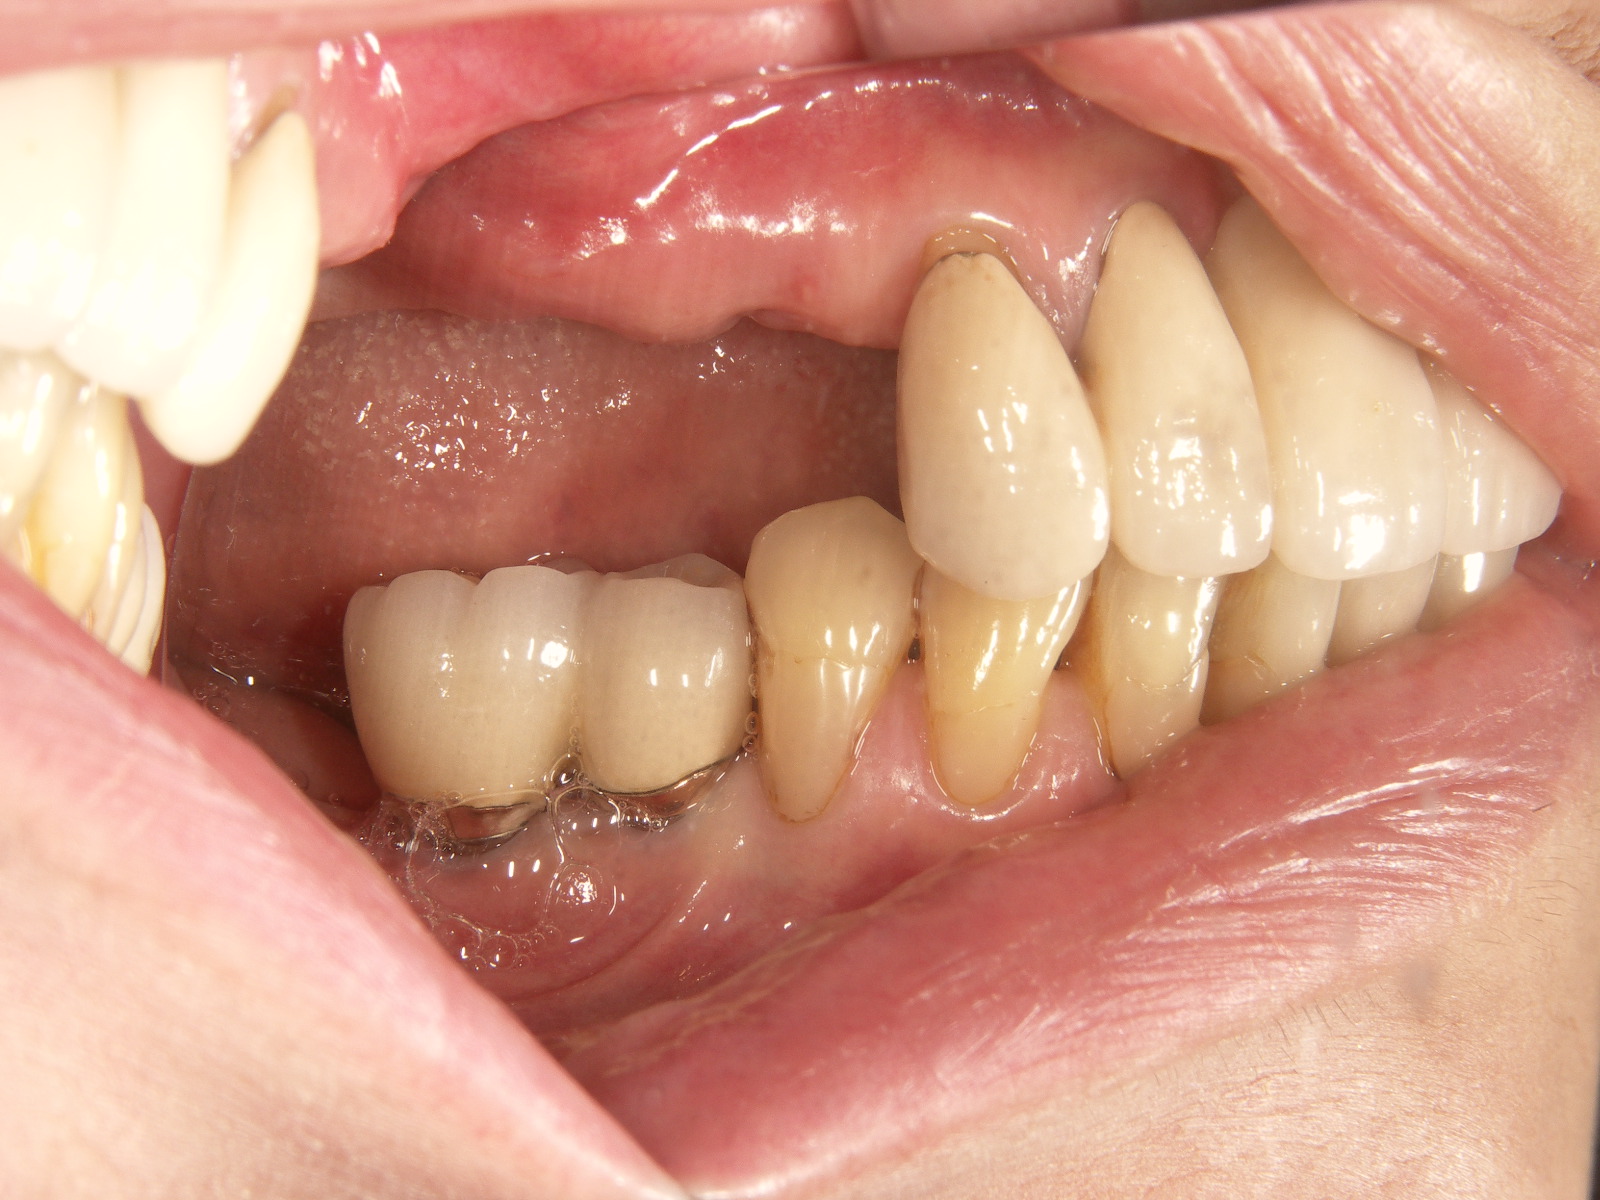

インプラント施術前

下あごの奥歯がなく、食いしばりが強いため前歯もすり減ってしまいました。

インプラント施術後

インプラントを6本埋入してかみ合わせも適当な高さに改善、前歯もセラミックをかぶせて見た目も改善しました。